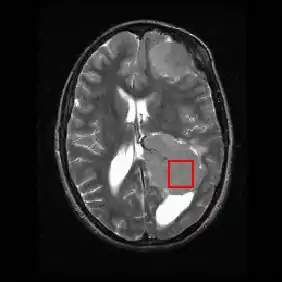

Shown below is an MRI brain scan (in the axial plane, that is slicing from front-to-back and side-to-side through the head) showing a brain tumor (meningioma) at the bottom right. The red box shows the volume of interest from which chemical information was obtained by MRS (a cube with 2 cm sides which produces a square when intersecting the 5 mm thick slice of the MRI scan).

Each biochemical, or metabolite, has a different peak in the spectrum which appears at a known frequency. The peaks corresponding to the amino acid alanine, are highlighted in red (at 1.4 ppm). This is an example of the kind of biochemical information which can help doctors to make their diagnosis. Other metabolites of note are choline (3.2 ppm) and creatine (3.0 ppm).